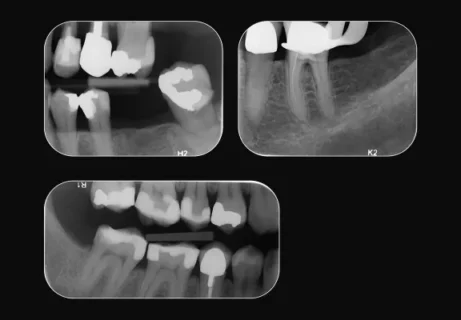

2D dentální nálezy

Okamžitě detekujte a diagnostikujte šest možných dentálních nálezů (kaz, periapikální léze, kořenový kanálek, okrajové netěsnosti, úbytek kosti, zubní kámen) pomocí funkce oblastí klíčového zájmu řízené umělou inteligencí ve vašich 2D intraorálních snímcích. Tato funkce je součástí přiloženého softwaru DTX Studio Clinic.